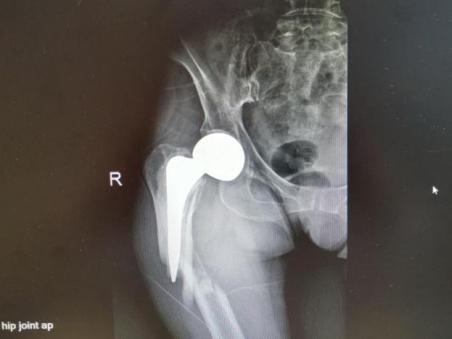

4月23日,贵州航天医院第58次晨读会由我院骨科副主任医师张艳金作学术交流,他以“加速康复指导下的快速手术”为题,详细讲解了老年股骨粗隆间骨折与儿童四肢骨折的临床诊疗难点,结合加速康复外科(ERAS)核心理念,重点阐述了ERAS理念在两大人群中的创新实践,实现患者入院后6至24小时内即可接受手术治疗。针对老年髋部骨折患者,提出通过多学科协作(MDT)与微创手术优化围术期管理,在确保安全前提下缩短术前等待时间,实施精准化麻醉及术后康复方案,可有效降低并发症发生率、改善患者生活质量和预后效果。在儿童骨折领域,强调微创术式与心理干预并行的双轨策略,既减少手术创伤对骨骼发育的影响,同时关注患儿心理疏导,实现生理功能与心理健康同步康复。并通过典型案例的影像学资料与随访数据,直观展示了ERAS理念指导下骨科治疗模式的创新成果。 贵州航天医院骨科 专家简介 赵学平 中共党员,骨科党支部书记、主任,主任医师 临床擅长:从事骨科临床工作30余年,对骨科常见疾病的诊治具有丰富的临床经验。 世界中医药联合会脊柱康复专业委员会常务理事,中华中医药学会整脊分会常务委员,中国中西医结合学会骨伤科分会肢体矫形功能重建与康复专家委员会常务委员,中国研究性医院学会骨科创新与转换专业委员会关节外科学组保髋工作委员会常委,中国康复技术转化及发展促进会骨外科与康复技术转化专业委员会常务委员,泛珠三角区域运动医学联盟(PPRD-SMA)理事会常务理事,中国研究型医院学会运动医学专业委员会委员,贵州省中医药学会整脊分会副主任委员,贵州省中西医结合学会银质针专业委员会副主任委员,贵州省康复医学会骨与关节专业委员会常务委员,贵州省人民医院骨科专科联盟常务理事,贵州省康复医学会骨内科专业委员会常务委员,中华医学会贵州省骨科学会委员,贵州省康复医学会脊柱脊髓专业委员会常务委员,贵州省运动医学分会委员,贵州省康复医学会骨与软组织肿瘤专业委员会委员,遵义市医学会创伤分会副主任委员,贵州省康复医学会骨内科专业委员会遵义地区分会常务委员,遵义市医疗事故鉴定、伤残鉴定、工伤鉴定、司法鉴定专家。 长期从事骨科临床研究及教学工作,在国家级、省部级杂志发表论文20余篇,SCI论文2篇,参与主编骨科专著2部,主持省部级科研项目2项,参与指导省部级、市级科研项目6项。 陈明勇 骨科副主任,副主任医师 临床擅长:从事创伤骨科工作约20年,对骨缺损、骨不连、骨肿瘤、肢体畸形等的肢体矫形重建及功能重建,慢性化脓性骨髓炎的根治治疗、糖尿病足的保肢治疗、快速康复理念(ERAS)下的老年骨折的诊治,四肢复杂骨折的诊治,四肢骨折等微创手术治疗具有丰富的临床经验。 2004年毕业于遵义医学院临床专业,曾在中国人民解放军总医院、广西医科大学第一附属医院、上海第六人民医院骨科进修。中国中西医结合学会骨伤科专业委员会横向骨搬移治疗糖尿病足及微血管网再生学组首届委员,遵义市医学会创伤分会常务委员。 瞿 辉 中共党员,骨科副主任医师 临床擅长:对骨科的常见病、关节外科、脊柱外科及运动医学疾病的诊治具有丰富的临床经验,熟练掌握骨科手术操作技术。 毕业于遵义医学院临床医学系,2005年前往广州中山大学第一附院骨显微医学部进修学习,2011年前往成都华西医院进修学习,并多次在省内外学习骨科相关知识,是中华医学会骨科分会会员。 赵兴东 骨科主任医师 临床擅长:擅长骨科的常见病及各种创伤、四肢骨折创伤修复、骨感染、手足疾病的诊治和手足体表畸形的矫形整复,熟练掌握骨科四肢骨病及创伤的手术操作技术,尤其在四肢关节复杂性损伤、手足外伤、组织缺损创面、难治创面的皮瓣修复方面及平足、高弓足矫形方面及四肢慢性疼痛诊治、康复方面具有丰富的临床经验。 硕士研究生,毕业于遵义医学院临床外科系,2015年前往山东省立医院手足外科进修学习;遵义市医学分会创伤分会第一、二届委员,遵义市手外科医学会第二委届员会常务委员;在省级及省级以上期刊发表文章9篇,参编著作2部,参与主持并完成市级课题1项,参与市级课题2项、省级课题1项。 张艳金 中共党员,骨科副主任医师 临床擅长:从事骨外科工作16年,对复合伤、多发伤的救治、四肢骨干骨折、关节周围骨折、骨肿瘤、骨髓炎等诊治具有丰富的临床经验。 中共党员,硕士研究生,2006年本科毕业于山西医科大学第二临床医学院,2011年研究生毕业于北京军区总医院;在“老年COPD患者合并髋部骨折的诊治”国际合作课题组研究两年,在老年髋部骨折的诊治方面具有丰富的经验,并发表论文6篇;主持遵义市级课题1项,承担遵义医科大学的临床教学工作,获得遵义医科大学优秀带教老师荣誉。编撰有《骨科疾病诊疗精粹》一书,开展2项新技术,编撰地方规范《务川自治县创伤骨科常见疾病诊疗规范》一书。 张俊凯 骨科副主任医师 临床擅长:从事骨科临床工作28年,对创伤骨折、骨感染、骨缺损、骨不连等外科诊治,四肢骨折的微创手术治疗,四肢复杂骨折(如关节内粉碎性骨折、多发骨折等)的损伤控制及手术治疗等具有丰富的临床经验。 1995年毕业于遵义医学院临床专业,2009年前往复旦大学附属医院骨科进修1年。 卢懿明 中共党员,骨科副主任医师 临床擅长:从事骨科工作18年,对创伤骨折、四肢骨折的微创手术治疗、四肢复杂骨折(如关节内粉碎性骨折、多发骨折等)的损伤控制及手术治疗,尤其是髋部骨折的PFNA等微创技术,踝关节骨折、膝关节周围骨折的Mipo微创技术等具有丰富的临床经验,开展了4项新技术,发明6项新型专利技术。 2005年毕业于遵义医学院临床专业,2017年,前往南方医科大学第三附属医院骨科进修半年,回院后运用Mipo技术对骨干骨折及干骺端骨折的治疗技术,同时积极开展骨盆骨折、髋臼骨折腹直肌外侧切口的应用;发表了多篇专业论文,经常参与省内外学术交流会授课,获得医院荣誉称号多个。 邬夏荣 骨科副主任医师 临床擅长:从事骨科工作16年,对四肢复杂骨折、骨肿瘤的诊治,尤其是足踝创伤、慢性踝关节损伤、平足症等诊疗具有丰富的临床经验。 2006年毕业于遵义医科大学临床医学专业,曾在陆军军医大学西南医院进修学习,发表多篇骨科学术论文。 余德怀 中共党员,骨科副主任医师 临床擅长:从事骨科工作10余年,对运动医学、骨关节、脊柱外科常见病、多发病的诊治具有丰富的临床经验。 硕士研究生,2011年毕业于遵义医学院临床医学专业,曾前往遵义医科大学附属医院运动医学专业进修学习;是贵州省医学会运动医学分会青年委员,西部关节镜联盟委员;发表多篇骨科学术论文。 冯 乾 骨科副主任医师 临床擅长:从事骨科工作近20年,熟练掌握骨科多发病及常见病的诊治,尤其对脊柱退变性疾病的诊断及治疗具有丰富的临床经验,主要研究脊柱微创相关治疗方式,能熟练开展椎间孔镜及UBE。 曾前往北京大学第三医院进修学习疼痛及椎间孔镜、首都医科大学友谊医院专业进修脊柱内镜;是贵州省康复医学会第三届脊柱脊髓专业委员会委员;发明专利3项、发表脊柱外科专业论文多篇。 赵小锋 中共党员,骨科副主任医师 临床擅长:从事骨科临床工作11年,对骨科常见病、多发病诊疗有较为丰富的临床经验,擅长脊柱相关疾病诊断及治疗,尤其是颈、腰、腿疼痛疾病诊断及治疗,擅长胸腰椎骨折微创经皮穿刺内固定术、经皮穿刺椎体成形术、经皮穿刺脊柱内镜下腰椎间盘摘除术、单纯开创腰椎间盘摘除术、腰椎滑脱复位椎间植骨椎融合内固定术、腰椎管狭窄减压融合内固定术及人工髋、膝关节置换术等。 2012年毕业于遵义医学院外科学专业硕士研究生,2019年参加“遵义市115医学人才精英计划”于上海交通大学第一附属医院培训学习,2023年于北京大学第三人民医院脊柱外科进修学习,曾获得遵义市优秀医师荣誉称号。 遵义市手外科第一届委员,遵义市医学会创伤分会第一届委员,遵义市医学会创伤分会第二届委员,贵州省康复医学会第三届脊柱脊髓专业会委员,遵义市医学会烧伤与整形外科学分会委员,发表论文5篇,其中国家级核心期刊1篇,SCI论文1篇,主持市级课题1项并结题,参与市级课题2项。 贵州航天医院骨科 简介 基本情况 贵州航天医院骨科组建于20世纪60年代,前身是以创伤和断肢(断指)再植闻名于世的上海市第六人民医院骨科,中国断肢(断指)再植的奠基者、中科院院士陈仲伟等著名专家、学者多次莅临科室指导医疗、教学,是贵州省最早拥有专业骨科技术科室之一,在70年代开展了贵州省首例断肢(断指)再植手术。组建50余年来,诊治患者已逾百万,挽救了无数的伤病员,成为了保障遵义地区人民群众健康的重要支撑。 经过几代人的不懈努力,今天的骨科,已由创伤骨科发展至骨病、骨肿瘤、骨结核等领域,现有脊柱外科、关节外科、四肢创伤、手足外科四个亚专科,成为了集医疗、教学、科研于一体的综合学科,是贵州省临床重点专科、遵义市临床重点专科、遵义市骨科临床医学中心、遵义市基层骨科专科联盟理事长单位。 科室目前开放床位110张,共有医护人员50余人,副高级以上专家18人,硕士研究生15人。拥有一流骨科医疗设备多台,每年不定期选派优秀技术骨干到全国各大知名医学院校进修、学习、参观、交流,并邀请国内、国外知名专家教授来院进行交流、指导,通过不断引进国内外先进的诊疗技术,科室医疗技术水平稳步提升,为广大人民群众提供了优质的医疗服务。 专科特色 骨一科 (一)骨缺损、骨不连的肢体与功能重建 胫骨横向骨搬移技术治疗糖尿病足: (二)慢性骨髓炎的根治治疗 (三)肢体缺血性疾病如糖尿病足、脉管炎的保肢治疗 (四)皮瓣修复 (五)复杂创伤的治疗 (六)老年髋部骨折及小儿骨折快速手术 老年髋部骨折: 骨二科 (一)胸腰椎骨折微创经皮椎弓根螺钉固定术 (二)老年性骨质疏松性患者腰椎滑脱脊柱内固定术(骨水泥螺钉) (三)V形双通道脊柱内镜技术(VBE)腰椎融合术治疗腰椎退行性疾病 (四)老年性骨质疏松性骨折(PVP/PKP)术 (五)人工髋关节置换术 (六)双侧股骨头坏死人工全髋关节置换 (七)右侧全髋置换术后假体周围骨折翻修 (八)人工膝关节置换术 (九)人工膝关节假体松动翻修 (十)关节镜技术 传统手术切口 关节镜技术切口 诊疗范围 骨一科 1.四肢创伤、矫形。 2.手、足踝外科。 骨二科 end